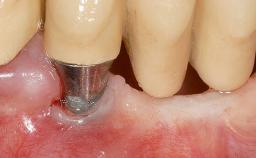

A 30-year-old woman was referred by her general dentist for evaluation of an esthetic complication related to previous implant treatment for congenitally missing maxillary lateral incisors. The patient’s chief complaint was the inadequate esthetic appearance of her smile. The case demonstrates the use of a combined approach to achieve optimal results. Two different flap designs - a tunnel technique and a coronally advanced flap - are employed based on the surgical objectives for the affected site.

Soft Tissue Grafting Yes